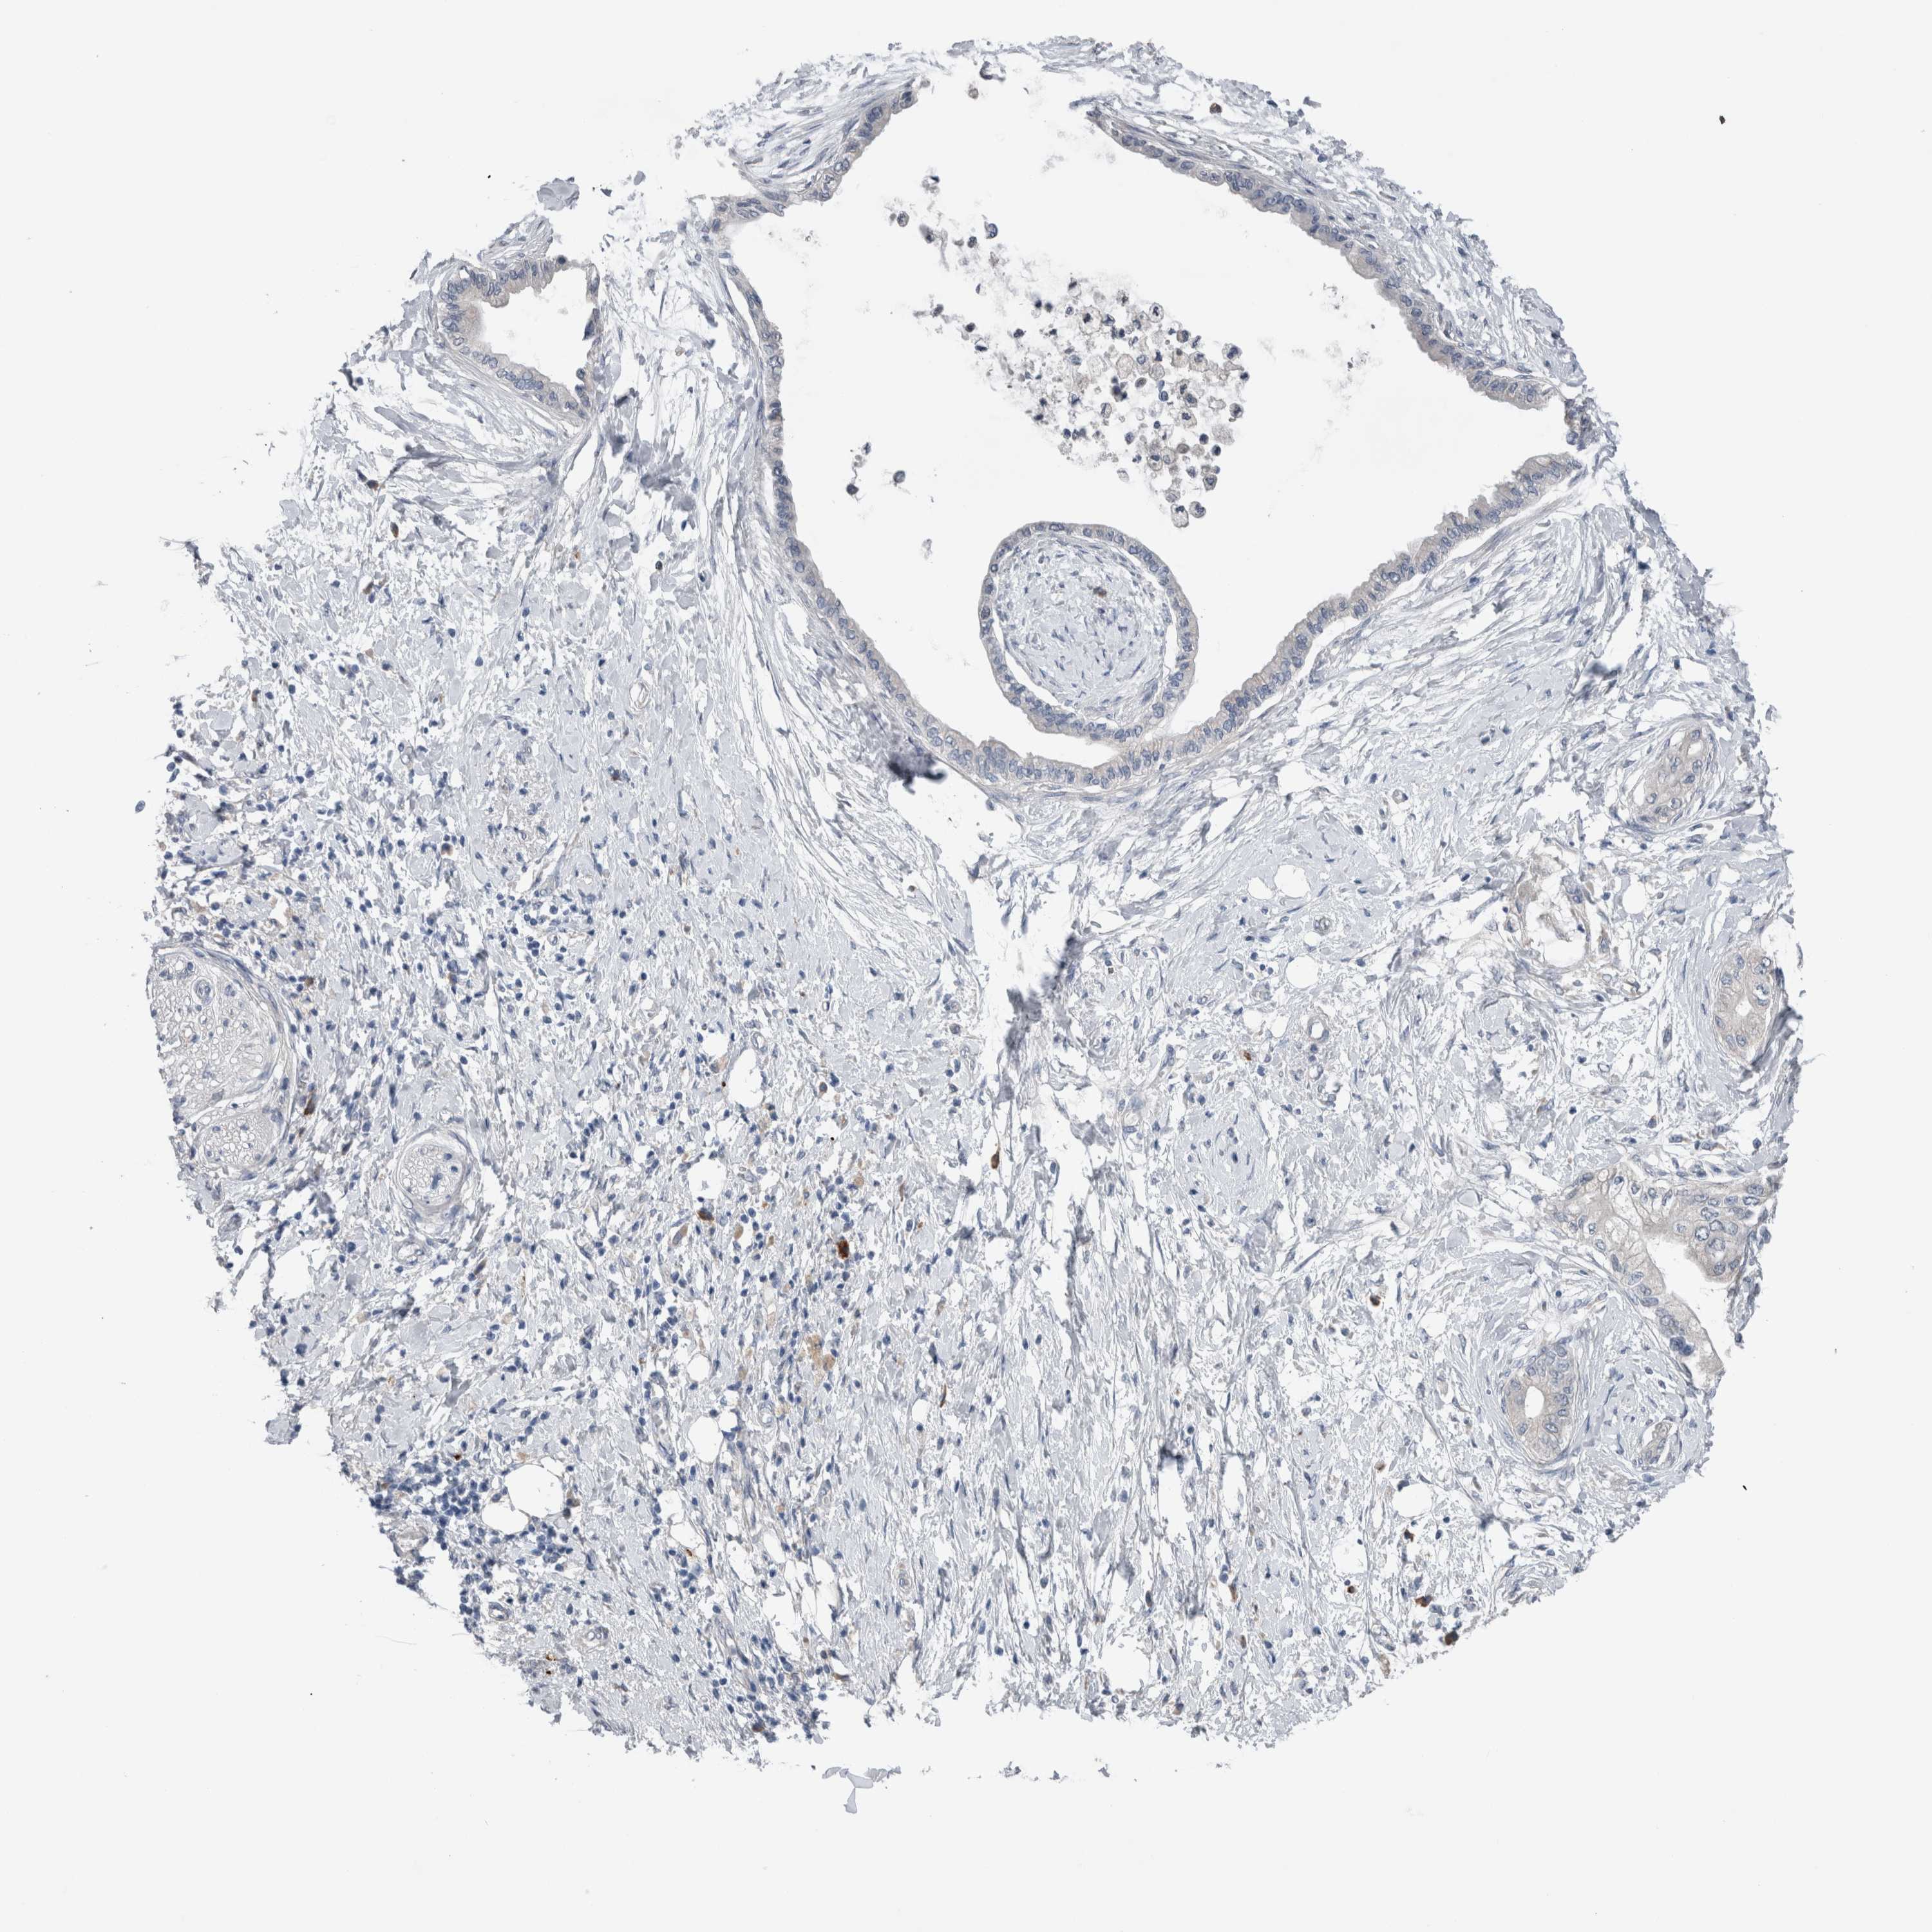

PANCREATIC CANCER - Protein expressioni

A mouse-over function shows sample information and annotation data. Click on an image to view it in a full screen mode. Samples can be filtered based on level of antibody staining by selecting one or several of the following categories: high, medium, low and not detected. The assay and annotation is described here.

Note that samples used for immunohistochemistry by the Human Protein Atlas do not correspond to samples in the TCGA dataset.

Antibody stainingi

Antibody staining in the annotated cell types in the current human tissue is reported as not detected, low, medium, or high, based on conventional immunohistochemistry profiling in selected tissues. This score is based on the combination of the staining intensity and fraction of stained cells.

Each image is clickable and will lead to virtual microscopy that enables deeper exploration of all samples and also displays staining intensity scores, fraction scores and subcellular localization as well as patient and tissue information for each sample.

Antibody HPA024343

Antibody CAB026182

Staining

High

Medium

Low

Not detected

Intensity

Strong

Moderate

Weak

Negative

Quantity

>75%

75%-25%

<25%

None

Location

Nuclear

Cytoplasmic/membranous

Cytoplasmic/membranous,nuclear

Adenocarcinoma, NOS